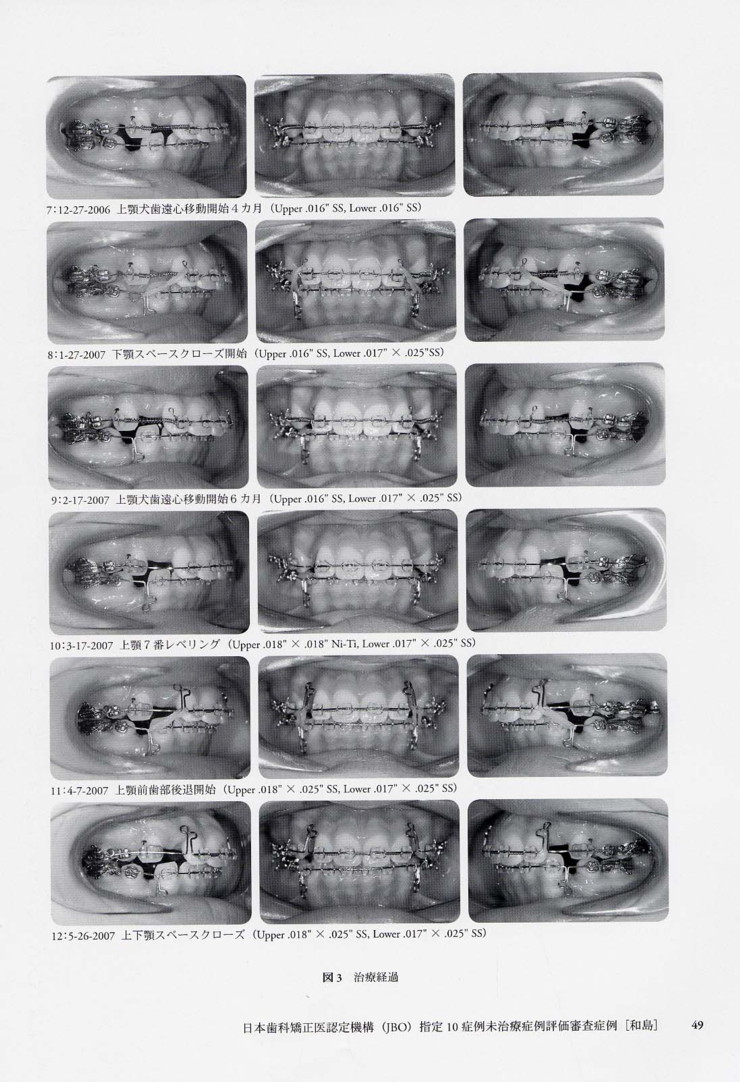

「日本歯科矯正医認定機構(JBO)指定

10症例未治療症例評価審査症例」